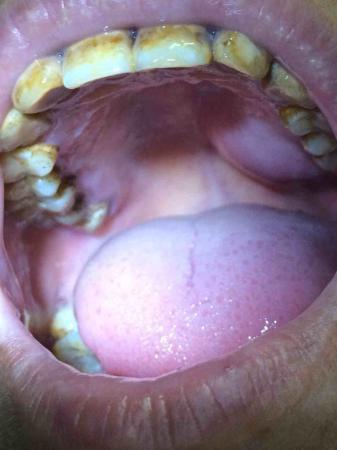

患者7,8年前口腔左上腭开始长肿块,进展缓慢,不痛,无其他不适,饮食正常,无消瘦。请大家帮忙诊断一下。